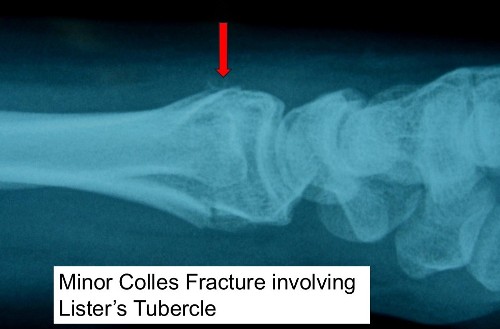

- A Colles fracture is a break in the distal radius (the main forearm bone near the wrist).

- This applies particularly when the fracture involves Lister’s tubercle – a prominence on the back of the radius around which the EPL changes direction

- The tendon may wear down and rupture, usually weeks – years after the fracture.